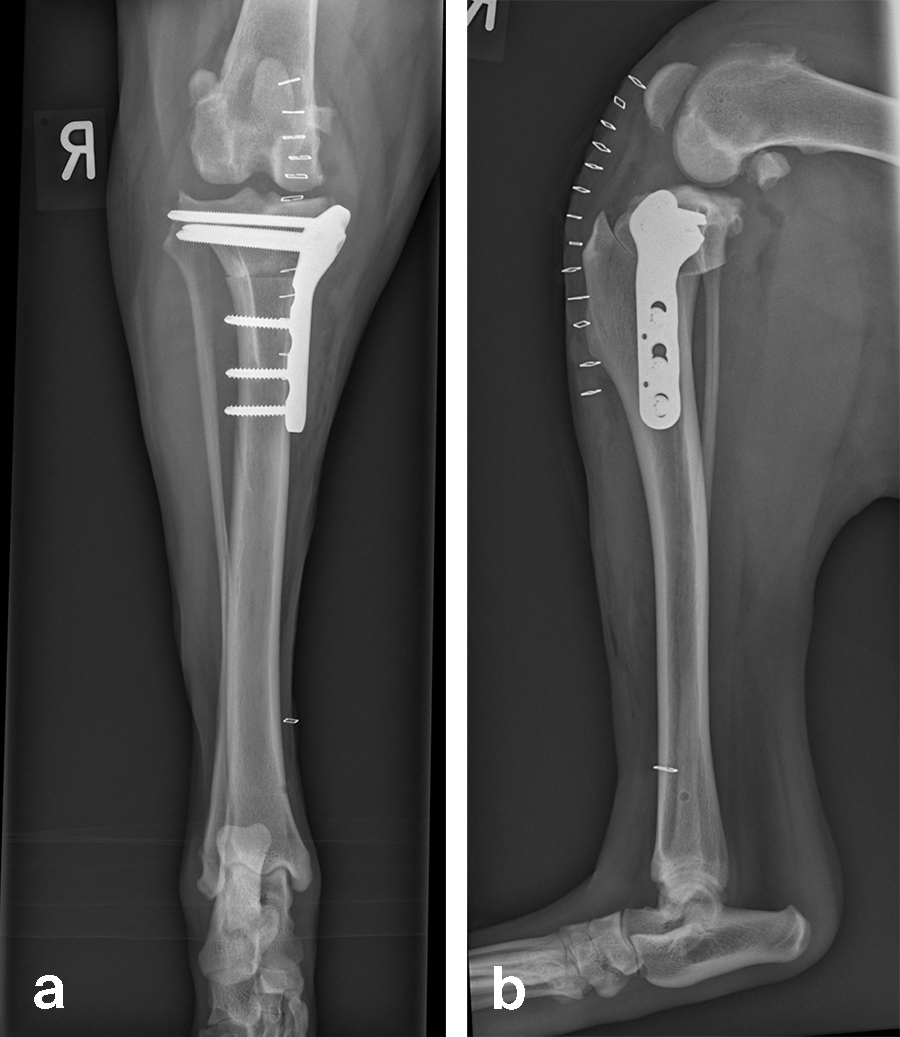

Left stifle arthroscopy was performed and a partial CCL rupture with incompetent remand was identified. The remaining CCL was debrided with a motorized shaver. The meniscus was healthy/non-injured based on visual inspection and probing. Arthroscopy portals were closed, and exposure of the proximomedial tibia was performed.

Based on preoperative templating, a 21 mm radial saw blade was used to perform an osteotomy of the proximal tibia. The plateau was leveled to a final target slope of 5° and the osteotomy was stabilized with a 3.5 mm ARC TPLO plate.

In Rosie’s case, the plate fit was excellent and the TPLO was performed without complication. Postoperative radiographs illustrate excellent plate position and screw placement and compression across all aspects of the osteotomy. Rosie recovered uneventfully from surgery and at the time of recheck (7 weeks postoperation) was using the operated limb without visible lameness. The knee examination was unremarkable, and radiographs demonstrated robust healing of the TPLO.

Follow-up x-rays at 8 weeks postoperatively revealed stable implants, stable bone segments, and healing of the osteotomy. The clinical outcome was satisfactory.